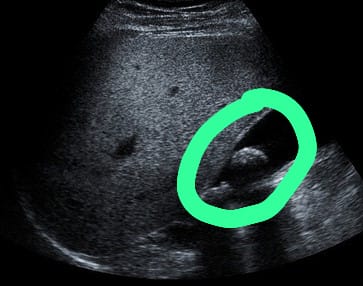

膽結石的形成與脂肪攝取有關,肥胖人士是高風險群組,蕭醫生解釋:「肥胖人士膽汁中有較高膽固醇濃度及分泌,且膽固醇合成機率也較高,故容易形成結石。除此之外,懷孕婦女由於膽汁飽和度增加,加上女性荷爾蒙的生理作用及膽囊弛張性(atonic)收縮不良,易使結石情況發生。在藥物方面,長期服用避孕丸,及停經後使用激素,臨床上發現有明顯較高的結石發生率。糖尿病人也易產生結石,一般歸因於膽汁中膽固醇分泌過多,及膽囊運動性不全(dyskinesia)。」膽結石沒有明顯症狀,必須透過醫學檢查判斷是否患有膽結石,蕭醫生表示:「腹部X光檢查簡單快捷,但若膽石過於細小往往不能察覺。腹部超聲波是最常用來查看膽石的檢查,可以查看其存在、位置、膽囊有否發炎,然而若病人腹部脂肪較厚會減低檢查的準確性。腹部電腦掃描或磁力共振檢查除了膽囊狀態,也可檢查腹部內各個器官,準確性不受病人體形影響。內視鏡超聲波可以確認膽石位置以及膽囊膽管狀態,不過具有入侵性風險,必須經過專科醫生評估,有需要才安排進行。」